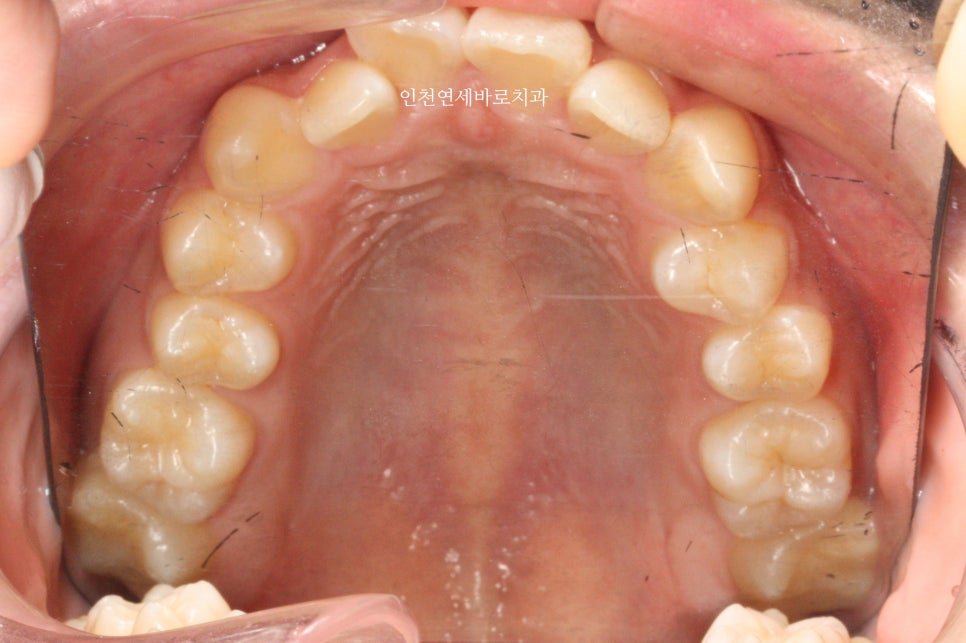

위아래 덧니가 있었고, 깊이 물리는 과개교합 및 중심선의 불일치 보이고 있습니다.

중심선 및 교합 모두 잘 유지되고 있습니다.

2년 후 역시 잘 유지되고 있으며

긴밀한 교합과 배열로 잘 유지되고 있다고 판단됩니다.